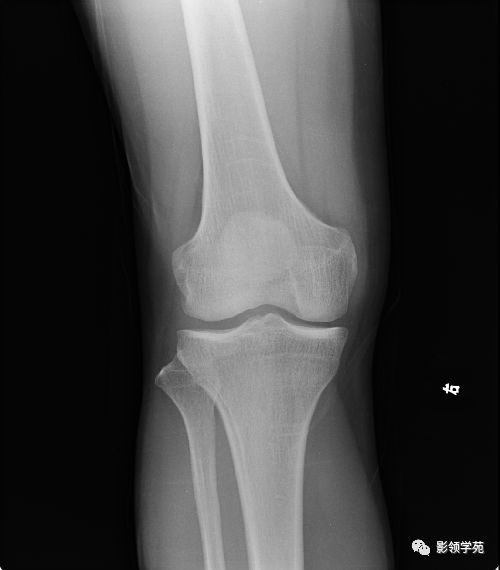

因此,從定義上來(lái)看,骨挫傷并不是骨折。其中,碾挫傷也被稱為離斷傷,分為不完全離斷和完全離斷兩種。然而,骨挫傷對(duì)工傷家屬來(lái)說(shuō)可能會(huì)造成很大的痛苦。因?yàn)楣谴靷ǔ?huì)伴隨著關(guān)節(jié)韌帶軟組織損傷等,最常...